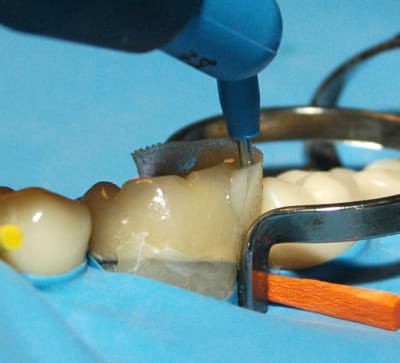

Enfin, sur l'image, on a utilisé des anneaux . Si les anneaux servent à plaquer la matrice contre la dent concernée, il agissent également comme écarteurs. Dans ce cas, c'est inutile. Pourquoi utiliser des anneaux, puisque l'on peut sans doute appliquer la matrice sur les parois axiales sans avoir besoin de tout cela. On gagnerait en visibilité et accessibilité.

Une fois la forme de la matrice figée, je pense qu'il faut la photopolymériser. Elle deviendra alors rigide, ce qui facilitera la mise en place du composite.

EverStick Net a existé en forme peu rigide, qui demandait un support d'adhésif pour la renforcer. Actuellement, le produit est modifié, il est souple, se laisse aplatir et de manipulation aisée.

Très facile à placer en interdentaire comme présenté sur les illustrations, à la limite il n'est pas utile de conserver un maximum d'émail, pour être sur que les anneaux puissent se caler. Un bon espace = une mise en place simple de la matrice. Elle peut également être découpée en bandelette,ainsi, être utilisée de manière conventionnelle.( très pratique pour les grands délabrements qui rendent l'usage de l'anneau impossible ).